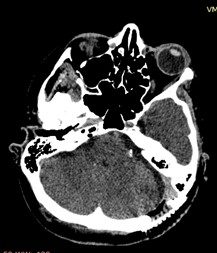

Основной этап хирургического вмешательства выполнялся нейрохирургами: профессором кафедры нейрохирургии д.м.н. профессором Гайворонским А.И. и старшим преподавателем кафедры к.м.н Чуриковым Л.И. После выполнения доступа к структурам задней черепной ямки в области мостомозжечкового угла визуализирован корешок левого лицевого нерва с предлежащими к нему сосудами. С помощью микрохирургической техники сосуды были поочередно отделены от лицевого нерва. Операция микроваскулярной декомпрессии завершена установкой двух тефлоновых прокладок между корешком нерва и компремировавшими его сосудами (рис. 4). При контрольной стимуляции отмечено исчезновение аномального мышечного ответа от лицевого нерва.

Рис. 4. Установленные тефлоновые прокладки на контрольной СКТ головного мозга